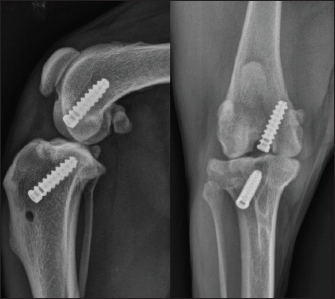

A 2-year-old female mixed-breed Shepherd weighing 15 kg, who suffered a trauma during play 3 months before, was presented with severe chronic lameness of the right hindlimb nonresponsive to NSAIDs. The orthopedic examination revealed a positive drawer test. The stress radiographs confirmed the suspicion of CdCL rupture with a displacement of the tibia relative to the femur (Fig. 1). A Liverpool osteoarthritis in dogs (LOAD) questionnaire was completed with the owner of the animal during the preoperative consultation, with a score of 22/52 indicating severe mobility impairment (Walton et al., 2013). A replacement of the CdCL by a synthetic UHMWPE ligament was decided using an arthroscopic approach.

Fig. 1. Radiographic views of the dog's right pelvic limb from side (left) and front (right) at the time of diagnosis.